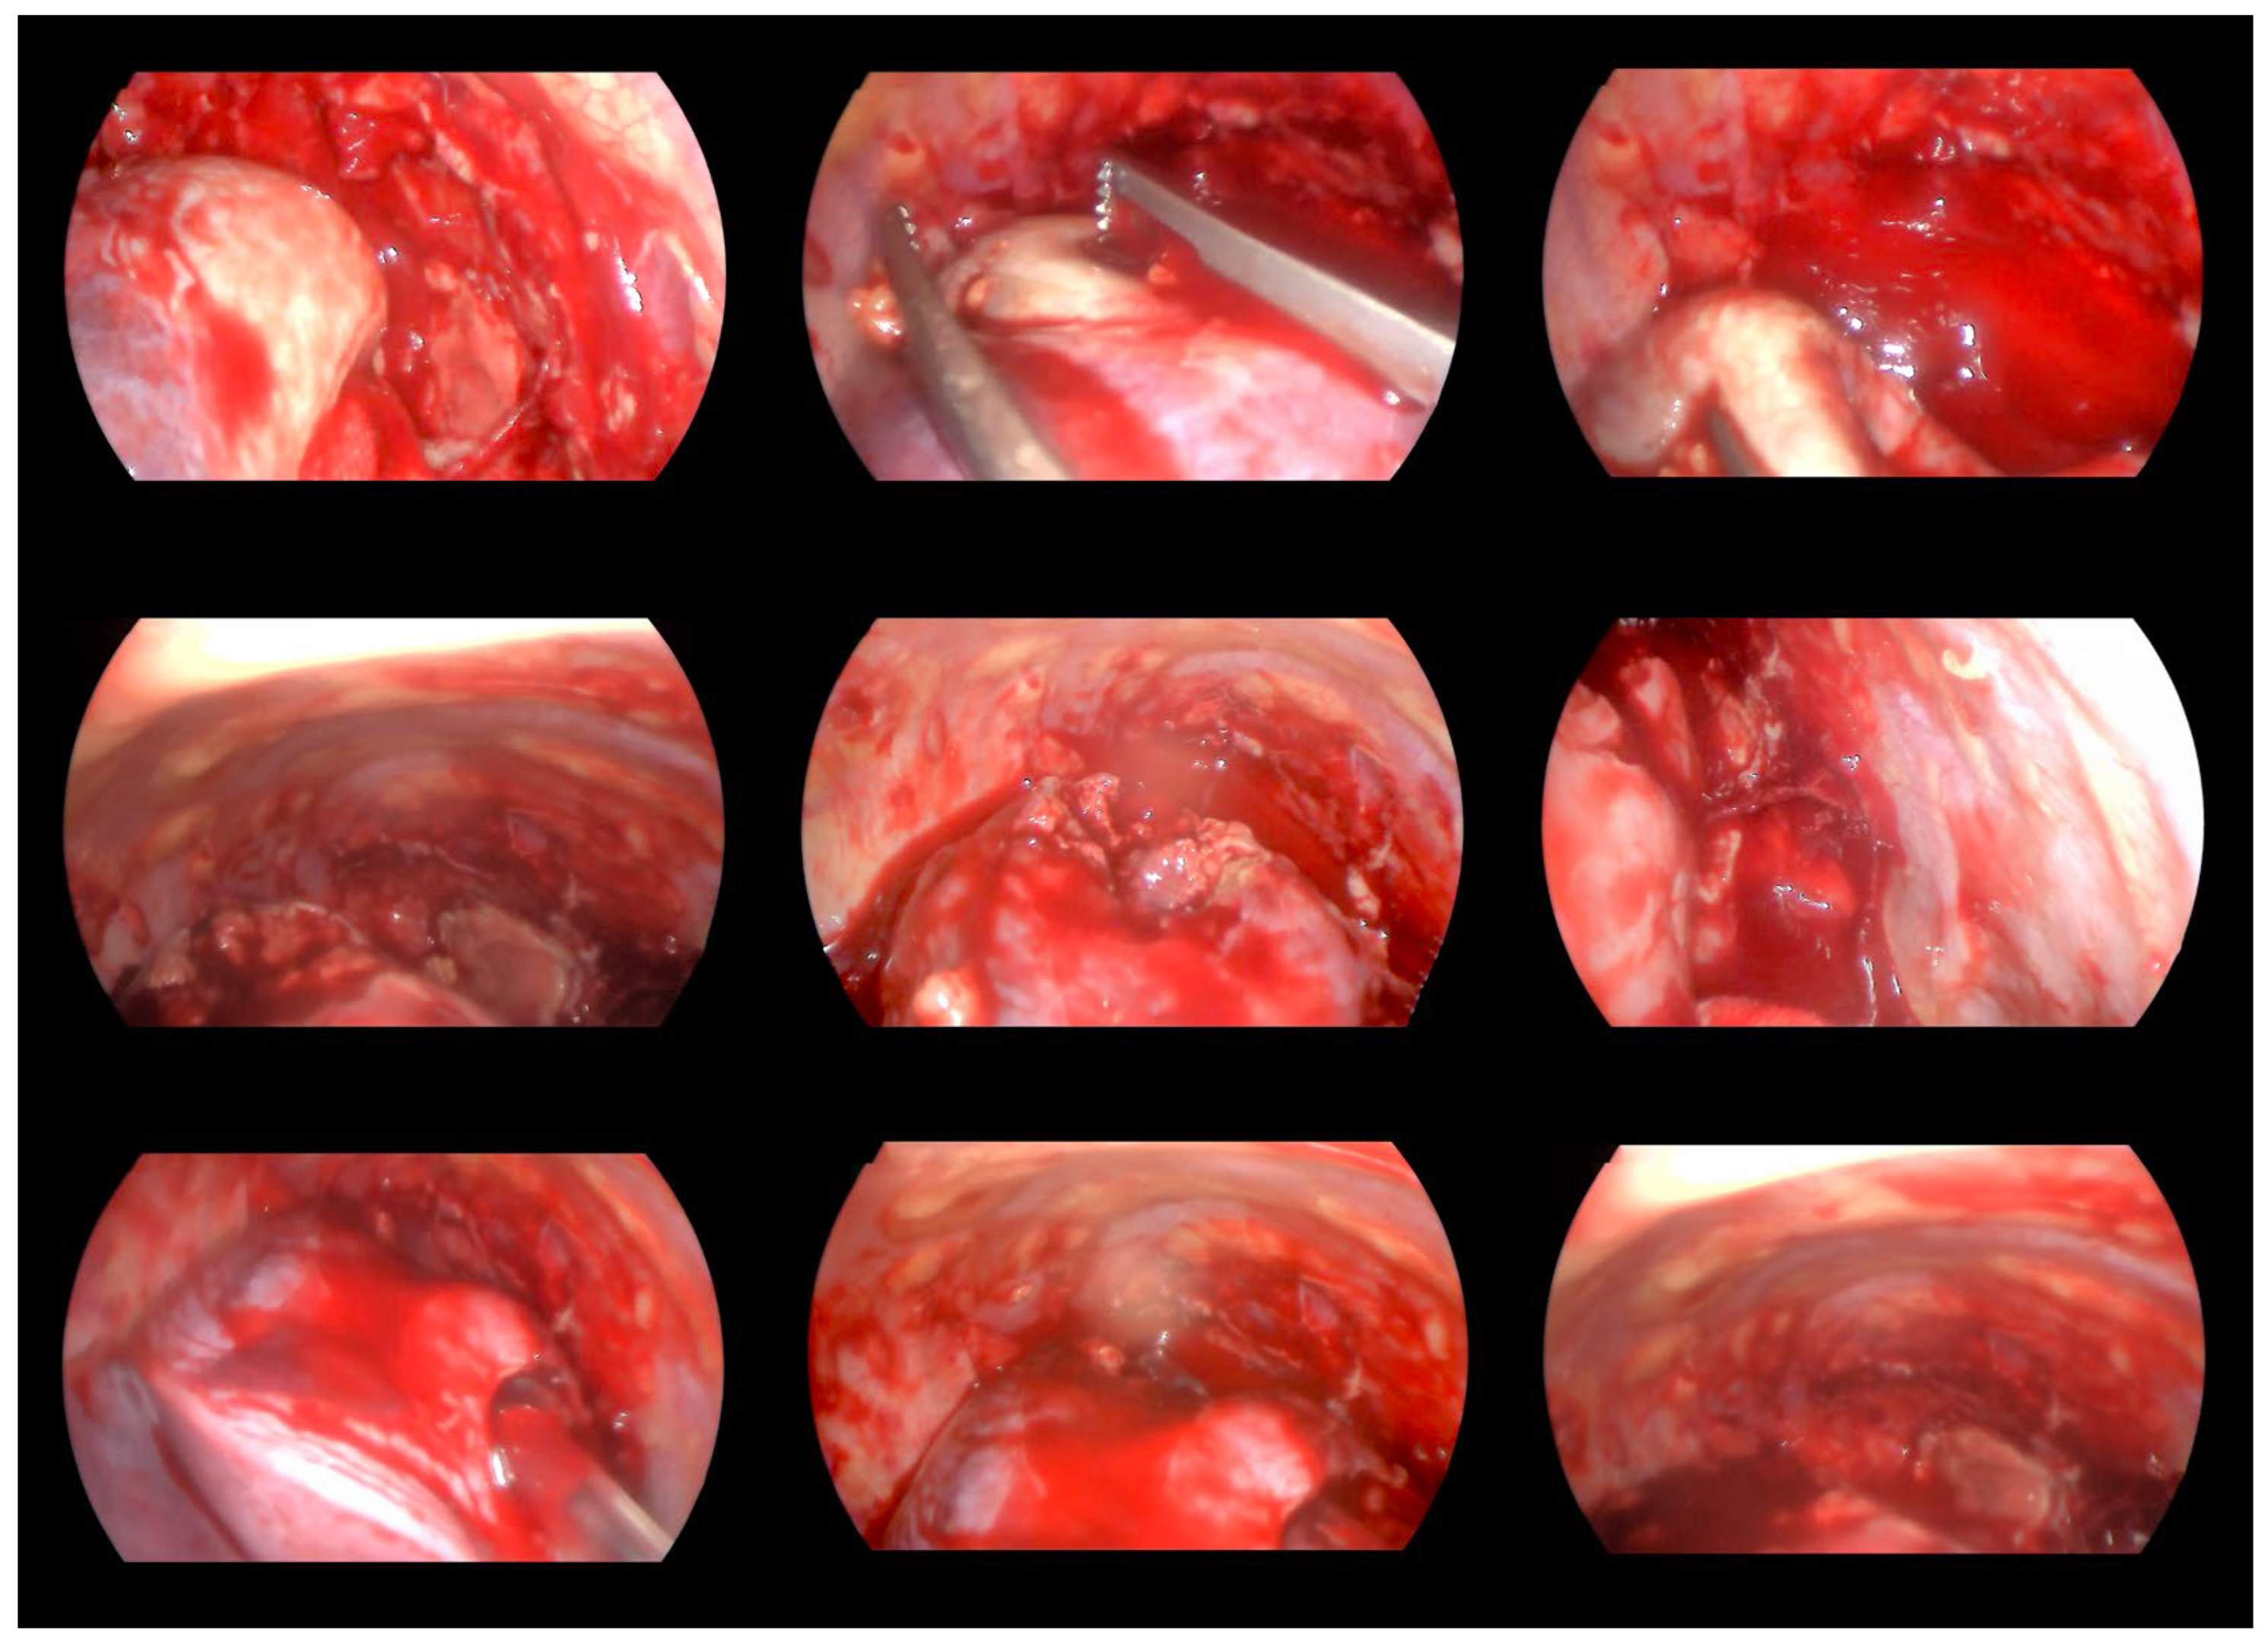

2. Case Report